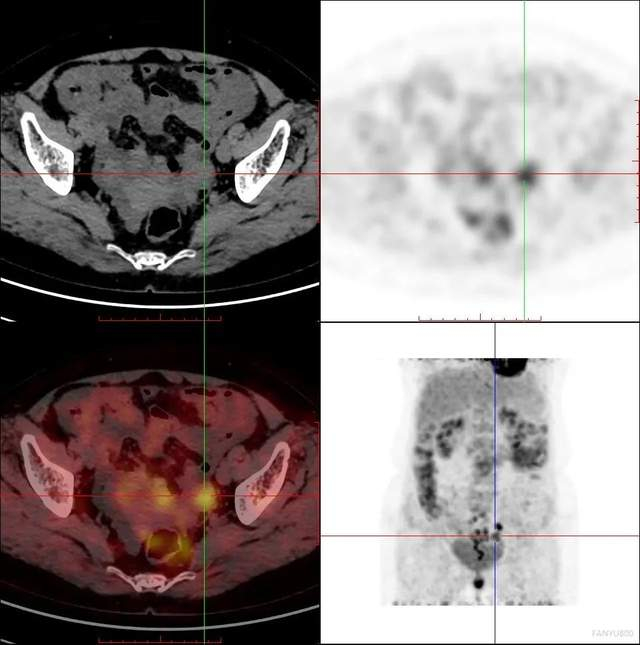

PET/CT检查卵巢癌

女性,60岁

相关病史:宫颈高级别鳞状上皮内病变(HSIL)锥切术后4月;否认结核及其他慢性病史。无其他临床症状。已绝经,无外伤史。2021-3-21日,患者因检查发现CA125渐进升高(250U/mL)后,在平安健康(检测)中心接受PET/CT检查。

PET/CT影像学表现

结论: 盆腔双附件区结节灶(左侧著)、右侧膈前上、肝脏包膜及腹盆腔多发结节灶、腹膜后多发淋巴结FDG代谢增高,考虑:卵巢癌(源于左侧卵巢可能性大)并上述部位多发转移瘤

PET/CT结论与病理结果对比

PET/CT结论:

考虑:卵巢癌(源于左侧卵巢可能性大)

手术病理结果:

卵巢癌

对比结论:

PET-CT实现肿瘤的精准定位及确诊。